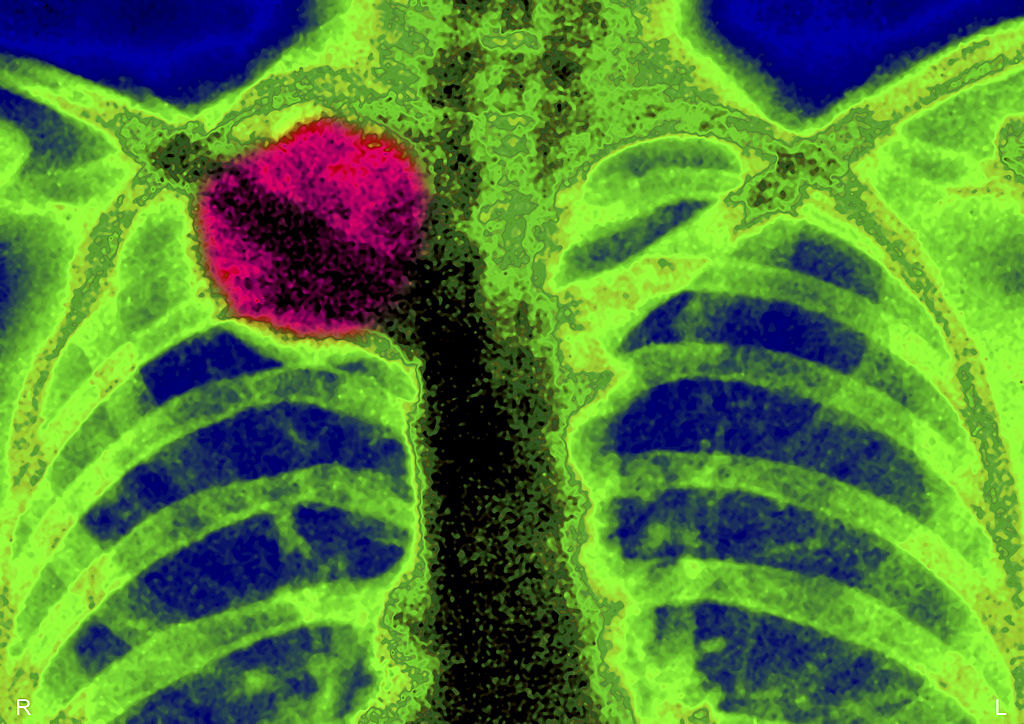

Cancer Was An Issue

Interestingly, bone cancer has been found in several remains of the early human species of Homo Kanamensis. One of the remains was discovered in Kenya by the leading paleoanthropologist, Louis Leakey, who was surprised to find a lump by a left tumor on the jaw.

This discovery proved that while most people might assume that cancer is more of a modern disease that came about after mankind became civilized, that's certainly not the case. It's been afflicting humans for far longer.